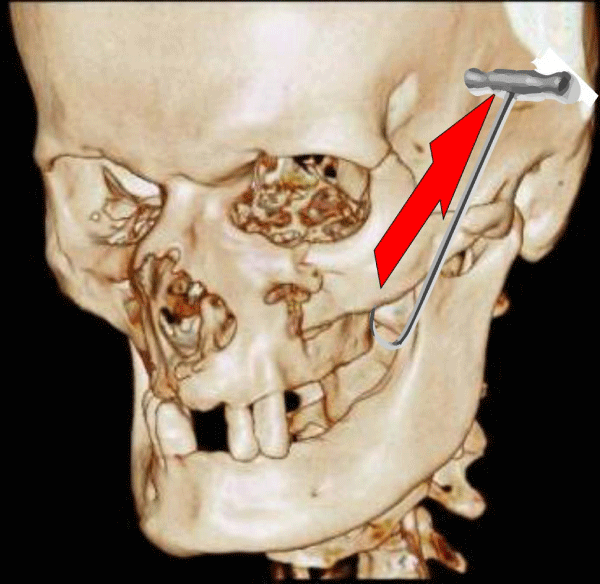

Isolated fractures of the zygomatical-arch impose mostly as three-point-fractures inverting the convex shape of the arch with an appearance of a collapsed bridge (Figure 6).

Figure 6:

Isolated zygomatical arch fracture with the typical three-fracture-spots appearance (right picture).

Surgery therefore should focus on minimal invasive transcutaneous fracture-reduction with only an option for stabilization of the reduction by osteosynthesis: a 3mm-incision is performed a finger-wide caudal of the zygoma-body into the cheek and a fracture-reduction hook inserted on the dorsal face of the zygoma-body. The infraorbital fracture-stage is palpated and the hook pulled strongly perpendicular to the zygoma-body outwards and upwards until the fractured segment snaps in with a characteristic “smacking” sound and the infraorbital fracture-stage can be palpated as fully reduced (Figure 7). Manual pressure loading of 2-3 N on the reduced fragment shows no mobility in almost 98% (unpublished data) which biomechanically is attributed to the self-stabilizing friction between the rough and spiky fracture-ends and the three dimensional stabilization of the tripod (enhanced by the unfractured zygomatic arch) and quadripod. The same surgical procedure is also applicable to isolated impression-fractures of the zygomatic arch which stabilizes itself by the bridge-like convexity but can be loaded for stability-check only with 1 N maximum (unpublished data). No dislocations of the transcutaneous reduced fractures were observed by masseteric pull-forces neither in patient-group Z of this study nor in younger patients treated the same way.